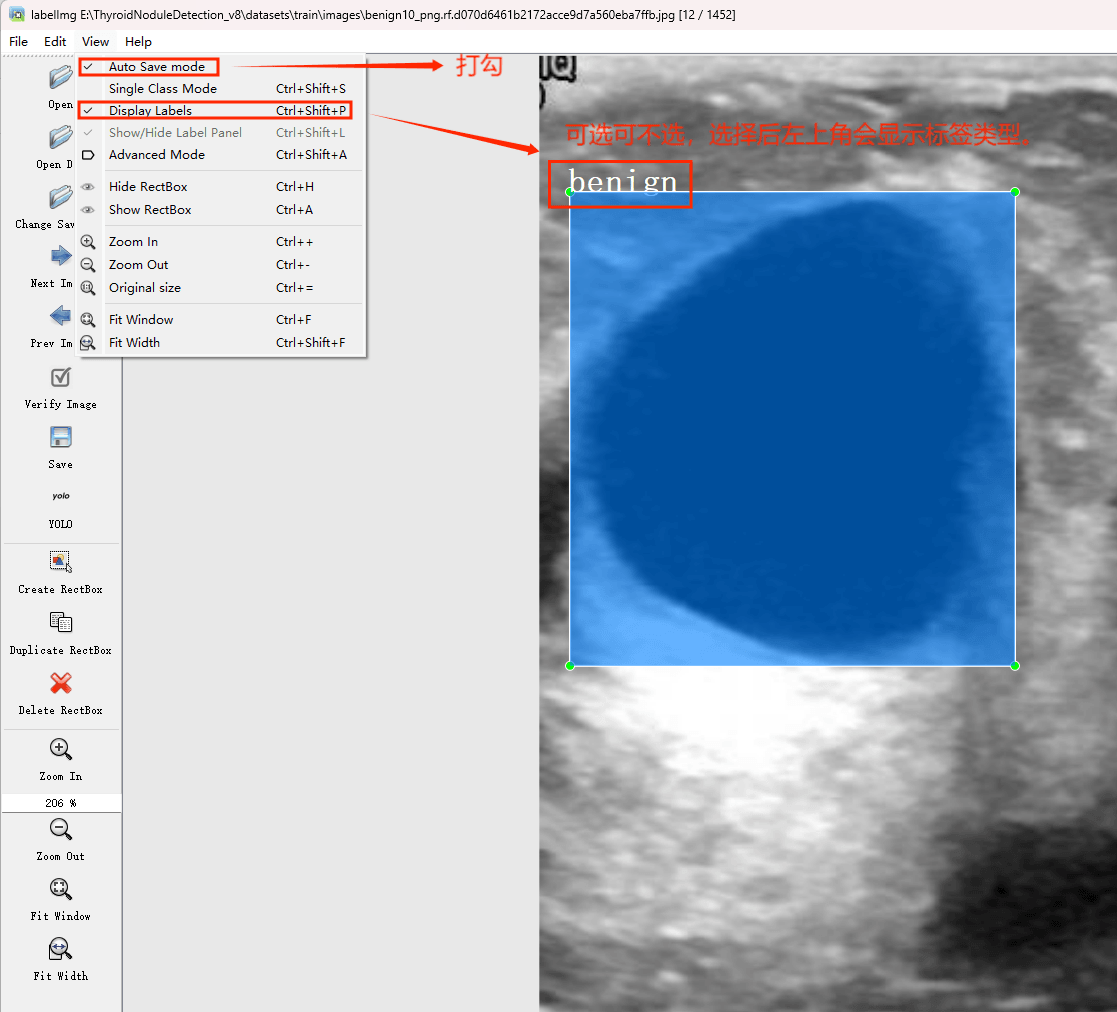

(1)labelimg:开源的图像标注工具,标签可用于分类和目标检测,它是用python写的,并使用Qt作为其图形界面,简单好用(虽然是英文版的)。其注释以 PASCAL VOC格式保存为XML文件,这是ImageNet使用的格式。此外,它还支持 COCO数据集格式。

初识labelimg

打开后,我们自己设置一下

在View中勾选Auto Save mode

接下来我们打开需要标注的图片文件夹

并设置标注文件保存的目录(上图中的Change Save Dir)

接下来就开始标注,画框,标记目标的label,然后d切换到下一张继续标注,不断重复重复。